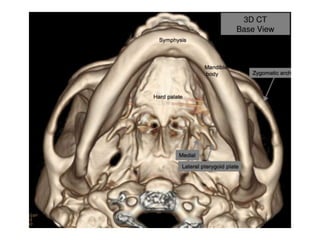

Key structures

J = Medial pterygoid

pslate

K = Lateral pterygoid

plate

N = Ethmoid,

perpendicular plate

3 = Sphenoid sinus

10 = Zygomatic arch

14 = Mandible, ramus

18 = mandible, angle